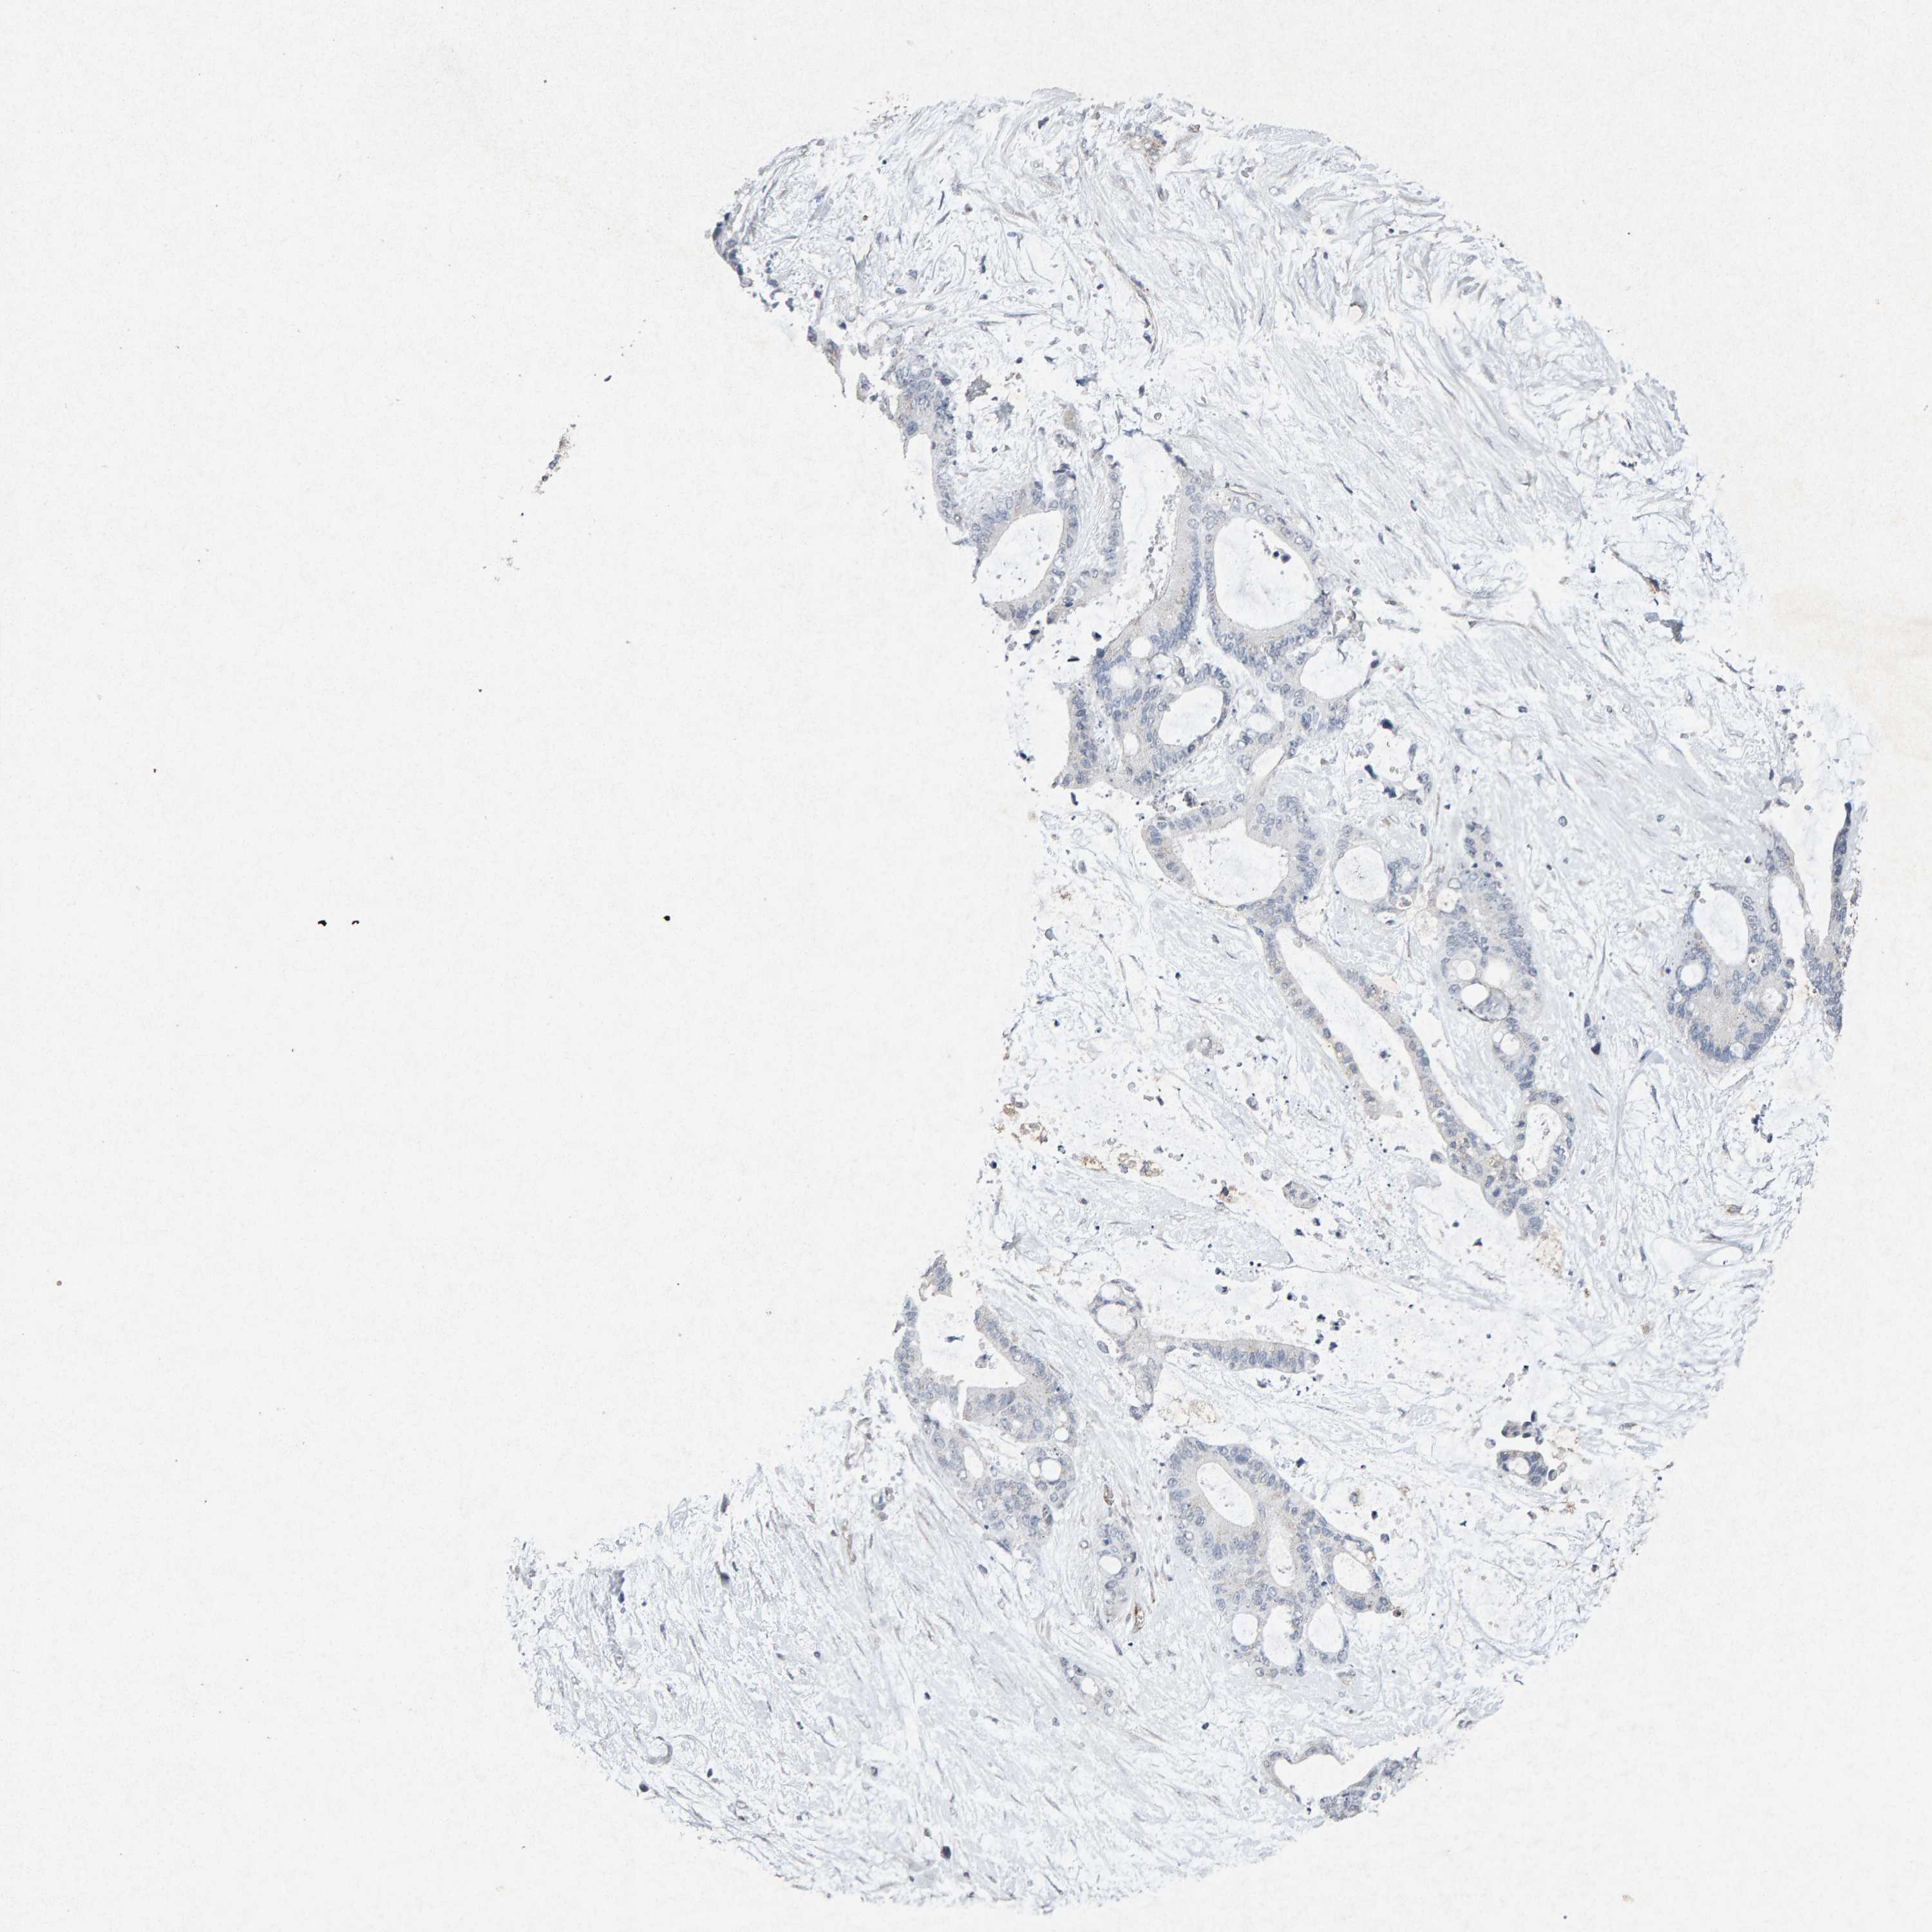

LIVER CANCER - Protein expressioni

A mouse-over function shows sample information and annotation data. Click on an image to view it in a full screen mode. Samples can be filtered based on level of antibody staining by selecting one or several of the following categories: high, medium, low and not detected. The assay and annotation is described here.

Note that samples used for immunohistochemistry by the Human Protein Atlas do not correspond to samples in the TCGA dataset.

Antibody stainingi

Antibody staining in the annotated cell types in the current human tissue is reported as not detected, low, medium, or high, based on conventional immunohistochemistry profiling in selected tissues. This score is based on the combination of the staining intensity and fraction of stained cells.

Each image is clickable and will lead to virtual microscopy that enables deeper exploration of all samples and also displays staining intensity scores, fraction scores and subcellular localization as well as patient and tissue information for each sample.

Antibody CAB022442

Antibody CAB022443

Staining

High

Medium

Low

Not detected

Intensity

Strong

Moderate

Weak

Negative

Quantity

>75%

75%-25%

<25%

None

Location

Nuclear

Cytoplasmic/membranous

Cytoplasmic/membranous,nuclear

Cholangiocarcinoma

Carcinoma, Hepatocellular, NOS